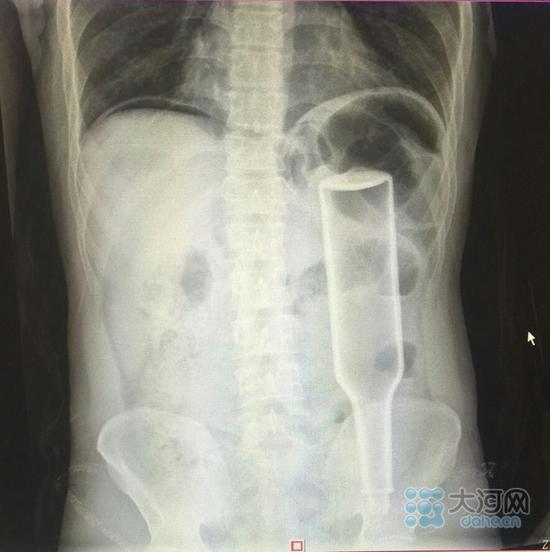

男子玩刺激将花露水瓶插入肛门 戳破肠子险致命

看这片子,花露水瓶子已经很“深入”了。看这片子,花露水瓶子已经很“深入”了。

在郑州务工的外地男子王某,下班到家后闲着没事儿干,于是将一个长18厘米的花露水瓶子塞进了自己的肛门,不过因为用力过猛,快感没来,瓶子却把直肠给戳破了,疼得受不了了,王某羞答答地来到郑州人民医院就诊,医生给他做了手术,现在已经出院。